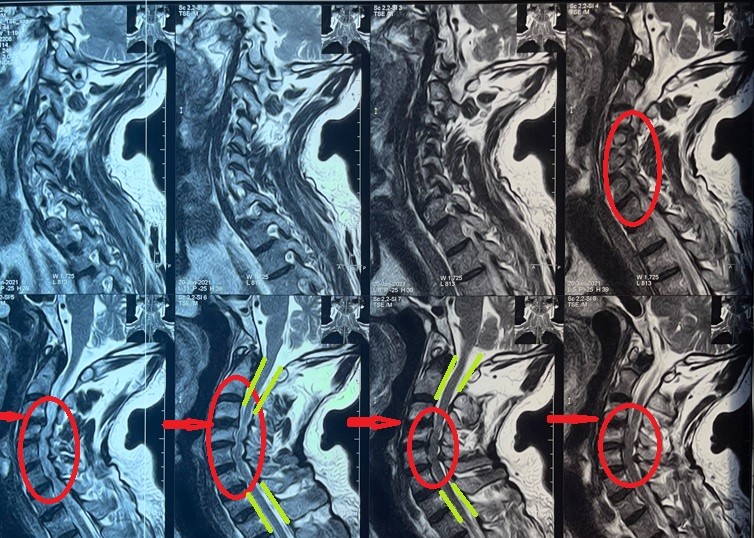

Fixation and dilatation of the cervical nerve canal to correct unsuccessful anterior cervical discectomy